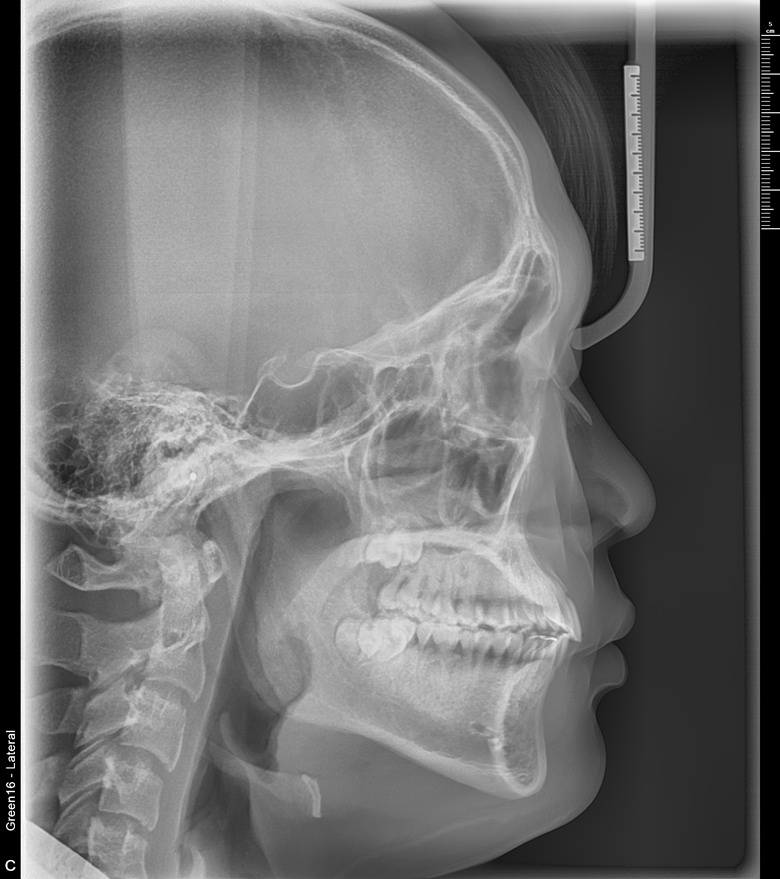

치료 전 사진입니다.